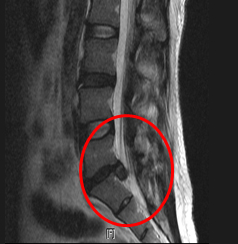

요추 추간판 수핵탈출증의 단계

팽륜

돌출

탈출

전위